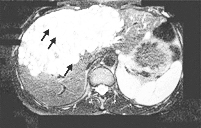

1例44岁妇女因右上腹间断不适10个月而就诊。体格检查发现其右上腹有一肿物。腹部超声和CT显示病人肝脏两叶有多发囊肿。MRI显示囊肿累及左叶内侧段和右叶前段(图A箭头)。酶联免疫法血清包囊虫和补体结合试验阳性(滴度1∶8)。病人随即接受根治性囊肿切除术。标本显微镜检查证实为泡状棘球蚴病。手术后给予阿苯达唑治疗,病人完全康复。